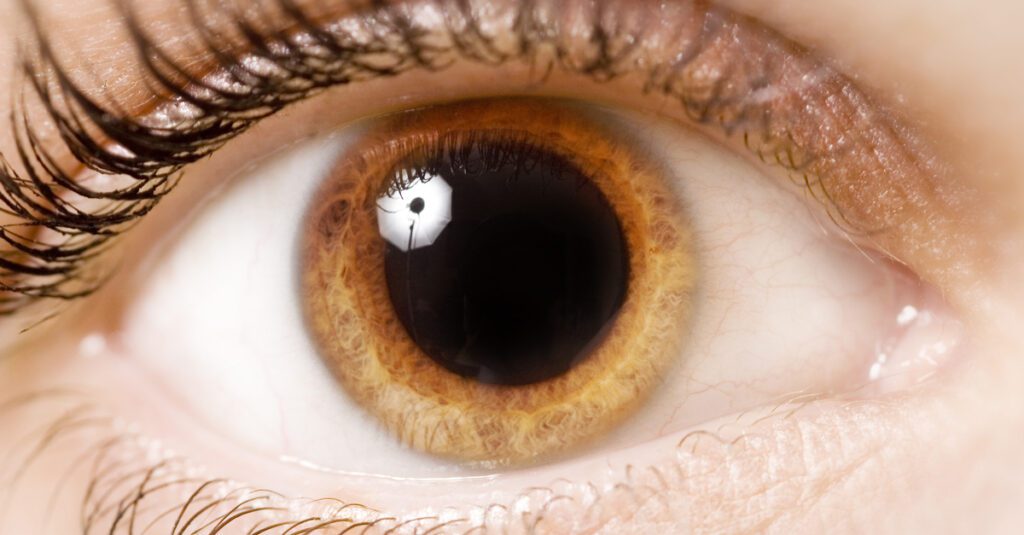

بؤبؤ العين و الأجراءات الجراحية المناسبة

ما هو البؤبؤ؟

بؤبؤ العين عبارة عن فتحات داكنة اللون في مركز عينيك تسمح بدخول الضوء. يمكن للأطباء أن ينظروا إلى بؤبؤك بحثًا عن أدلة حول صحتك.

يمكن أن يساعد حجم بؤبؤ العين وكيفية تفاعلهم مع الضوء في تشخيص بعض المشكلات الصحية. على سبيل المثال إذا تعرضت لضربة في الرأس وكان أحد بؤبؤك أو كلاهما متسعًا – أكبر من الطبيعي – فقد يكون ذلك علامة على إصابة دماغية خطيرة .

ما هو تقبض بؤبؤ العين؟

الدائرة السوداء في وسط عينك هي حدقة عينك. يتغير حجمه آلاف المرات في اليوم. عندما تكون في ضوء خافت يكبر للسماح بدخول المزيد من الضوء. وعندما تكون في ضوء ساطع يتقلص لحماية عينك وإبعاد الضوء.